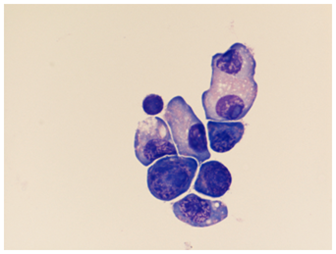

Contrast-enhanced MRI imaging of the brain and spinal cord revealed a dramatic pattern of diffuse meningeal enhancement including around the brainstem and cerebellum, in the basal cisterns, particularly around the optic chiasm and in the interpeduncular cistern, and also throughout the bilateral sylvian cisterns and to the left and right vertex. There was extensive cranial nerve enhancement bilaterally. Matching the right visual deficit, there was marked enhancement and thickening of the meningeal sheath of the right optic nerve and minimal enhancement of the left optic nerve sheath, especially in the vicinity of the optic chiasm. There was also enhancement of the cervical and lumbosacral spinal cord compatible with metastatic multiple myeloma and myelomatous meningitis (Figure 2).

Figure 2 MRI revealed marked diffuse meningitis especially involving the meningeal sheath of the right optic nerve, optic chiasm, and multiple other cranial nerves bilaterally.